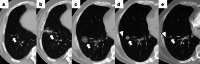

Image-guided percutaneous lung ablation has proven to be a valid treatment alternative in patients with early-stage non-small cell lung carcinoma or oligometastatic lung disease. Available ablative modalities include radiofrequency ablation, microwave ablation, and cryoablation. Currently, there are no sufficiently representative studies to determine significant differences between the results of these techniques. However, a common feature among them is their excellent tolerance with very few complications. For optimal treatment, radiologists must carefully select the patients to be treated, perform a refined ablative technique, and have a detailed knowledge of the radiological features following lung ablation. Although no randomized studies comparing image-guided percutaneous lung ablation with surgery or stereotactic radiation therapy are available, the current literature demonstrates equivalent survival rates. This review will discuss image-guided percutaneous lung ablation features, including available modalities, approved indications, possible complications, published results, and future applications.